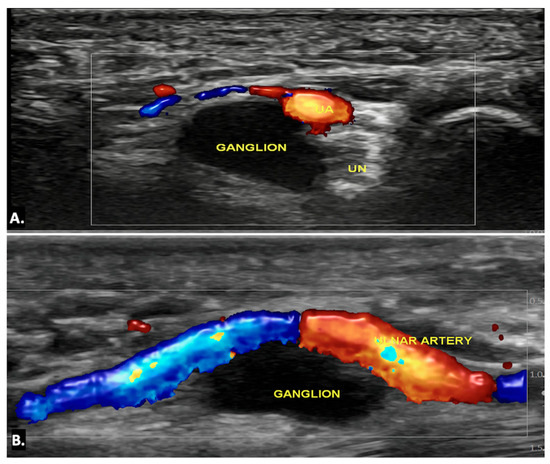

Ultrasound imaging is often the first and typically the only imaging modality required to diagnose a ganglion cyst. On ultrasound imaging, ganglion cysts appear as well-circumscribed anechoic or hypoechoic lesions with posterior acoustic enhancement. They may also show communication with nearby joints or tendon sheaths, which helps confirm their origin. Doppler ultrasound is useful to exclude the possibility of a vascular lesion, such as an aneurysm, by demonstrating an absence of blood flow within the cyst. Additionally, internal signals within the lesion on Doppler may raise suspicion for a sinister aetiology, such as a sarcoma, warranting further investigation (Figure 6) (Video S1) [13,14].

Figure 6.

(A) Axial and (B) longitudinal colour Doppler ultrasound image showing an anechoic cystic lesion within Guyon’s canal, displacing the ulnar artery—likely a simple ganglion cyst.